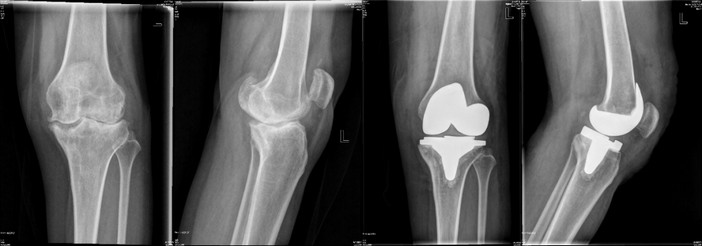

手術(shù)治療

林×,女,51歲,嚴重膝關(guān)節(jié)骨關(guān)節(jié)炎行人工全膝關(guān)節(jié)置換術(shù),術(shù)后6周恢復正常勞動。